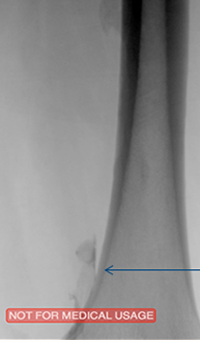

Xray of Iliofemoral thrombus pre-treatment and Power Pulse™ delivery

Iliofemoral thrombus pre-treatment (left) and Power Pulse delivery (right)

Xray of veins post-ZelanteDVT mechanical thrombectomy.

Post-ZelanteDVT  Mechanical Thrombectomy

Xray of veins post-ZelanteDVT runtime 415 seconds.

Post-ZelanteDVT runtime 415 seconds

Images Courtesy of Charles Wyble M.D. – Vascular Surgical Associates, Marietta, Georgia – January 5, 2016